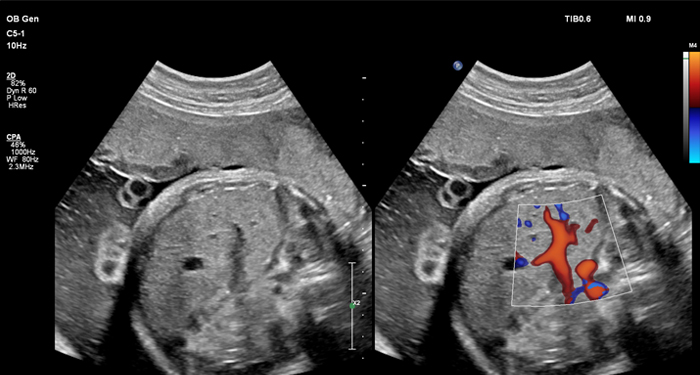

At the touch of a button, the new MaxVue high-definition display brings extraordinary visualisation of anatomy with 1,179,648 additional image pixels compared to a standard 4:3 display format mode. MaxVue enhances ultrasound viewing during interventional procedures and provides 38% more viewing area to optimise the display of dual, side/side, biplane, and scrolling imaging modes.